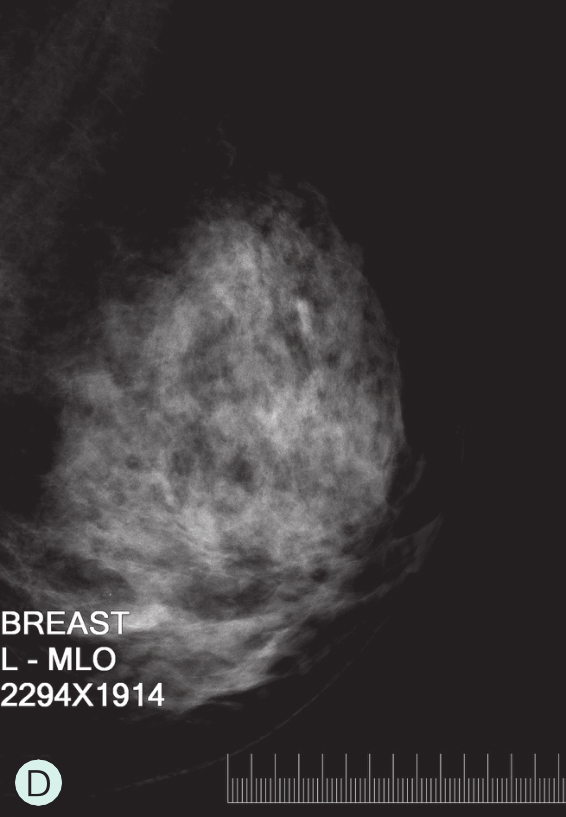

D级:极度致密型(降低乳腺钼靶摄影的敏感性)(图1-3-1D、图1-3-2D、图1-3-3D)。

图1-3-1 乳腺X线不同乳腺密度

A.脂肪型;B.散在致密型;C.不均匀致密型;D.极度致密型